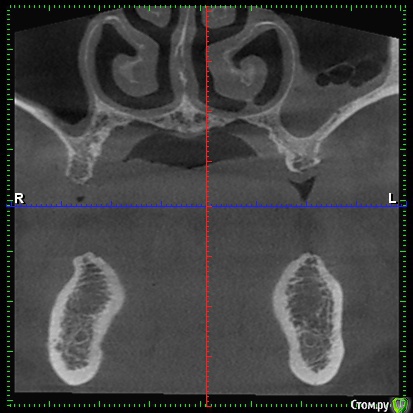

DenisV Опубликовано 11 декабря, 2017 Поделиться Опубликовано 11 декабря, 2017 Доктора, пациент обратился с целью установки имплантатов. На клКТ обнаружено затенение пазухи, отправлен к ЛОР на консультацию. Что это? синусит? ретенционка? Ссылка на комментарий

Большой Зеленый Опубликовано 12 декабря, 2017 Поделиться Опубликовано 12 декабря, 2017 Гайморит . 5 Ссылка на комментарий

Paganini Опубликовано 12 декабря, 2017 Поделиться Опубликовано 12 декабря, 2017 (изменено) Это синусит. И жалоб нет? Изменено 12 декабря, 2017 пользователем Paganini Ссылка на комментарий

колесников Опубликовано 12 декабря, 2017 Поделиться Опубликовано 12 декабря, 2017 Пузырьки газа в жидкости. Ссылка на комментарий